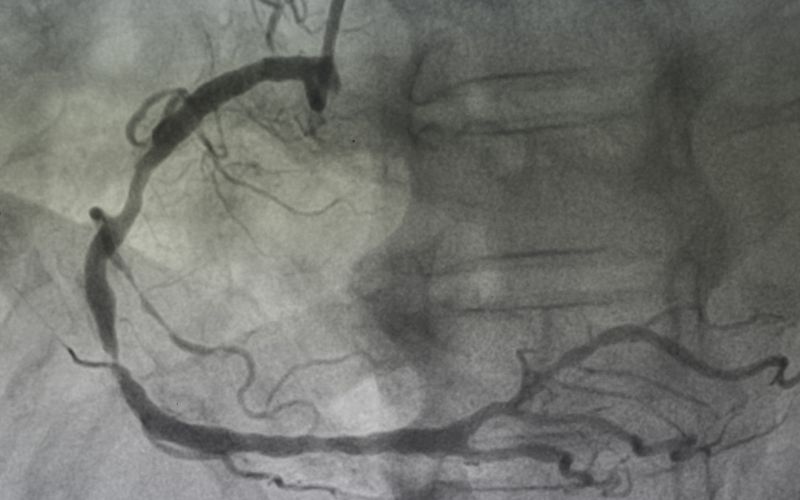

Sam zabieg koronarografii, choć jest procedurą inwazyjną, przeprowadzany jest w znieczuleniu miejscowym, a pacjent pozostaje przytomny i może komunikować się z zespołem medycznym. Zwykle trwa od 20 do 40 minut, jeśli ma charakter wyłącznie diagnostyczny. Lekarz ocenia stan lewej tętnicy wieńcowej (LCA) oraz prawej tętnicy wieńcowej (RCA).

- Ocena i ewentualne leczenie – aparat rentgenowski rejestruje przepływ kontrastu (angiogram), uwidaczniając wszelkie zwężenia. Jeśli badanie ujawni istotne zmiany (powyżej 70% światła naczynia), procedura może płynnie przejść w fazę terapeutyczną.